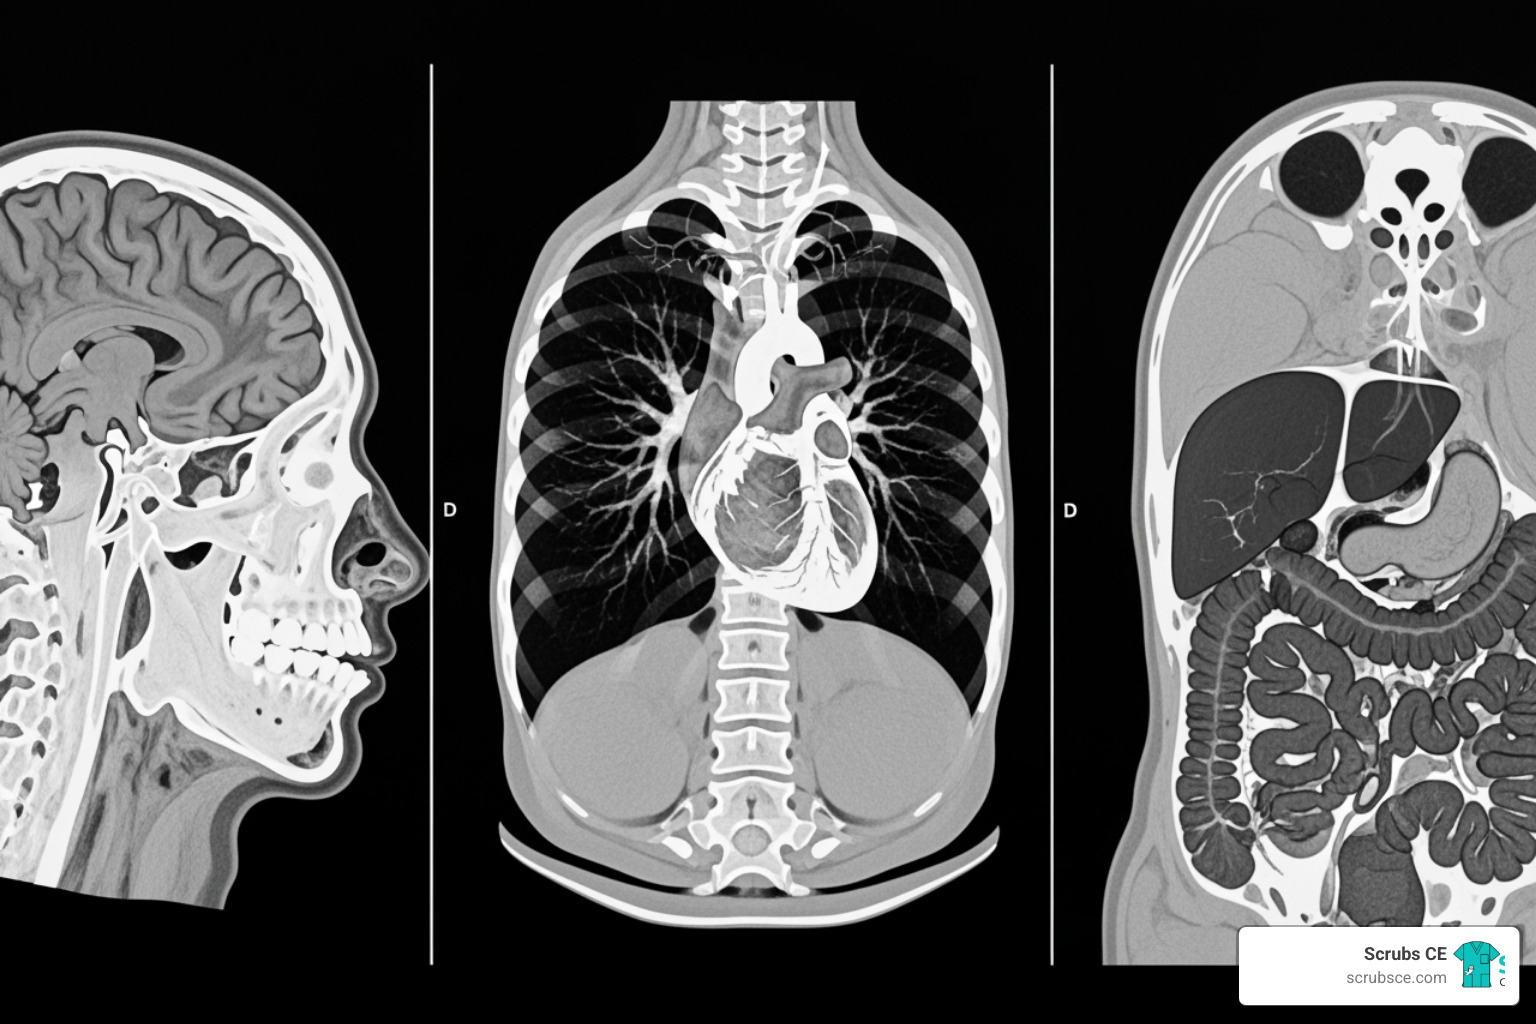

Computed tomography uses a series of x-ray images to create detailed cross-sectional “slices” of the body, which can be digitally stacked into 3D views. As CT technology evolves with innovations like dual-energy scanning and AI, continuing education is vital for delivering better patient care and maximizing career potential—not just for checking licensure boxes.

CT Principles & Instrumentation courses cover the mechanics and physics of CT, including X-ray generation, scanner components (gantry, tube, detectors), and reconstruction techniques.

Image Formation & Evaluation courses teach you to optimize image quality by working with Hounsfield Units, windowing, resolution, and artifact identification. Understanding your PACS (Picture Archiving and Communication System) is also covered.

Sectional Anatomy courses are essential for accurate patient positioning and recognizing anatomical variations.

When it comes to specific procedures, the options get really interesting. Cardiac CT courses focus on imaging the heart, as detailed in our Cardiac and Vascular Computed Tomography course. CT Angiography courses explore imaging blood vessels. You’ll also find specialized courses for abdomen & pelvis, head and spine imaging, musculoskeletal applications, and chest procedures.